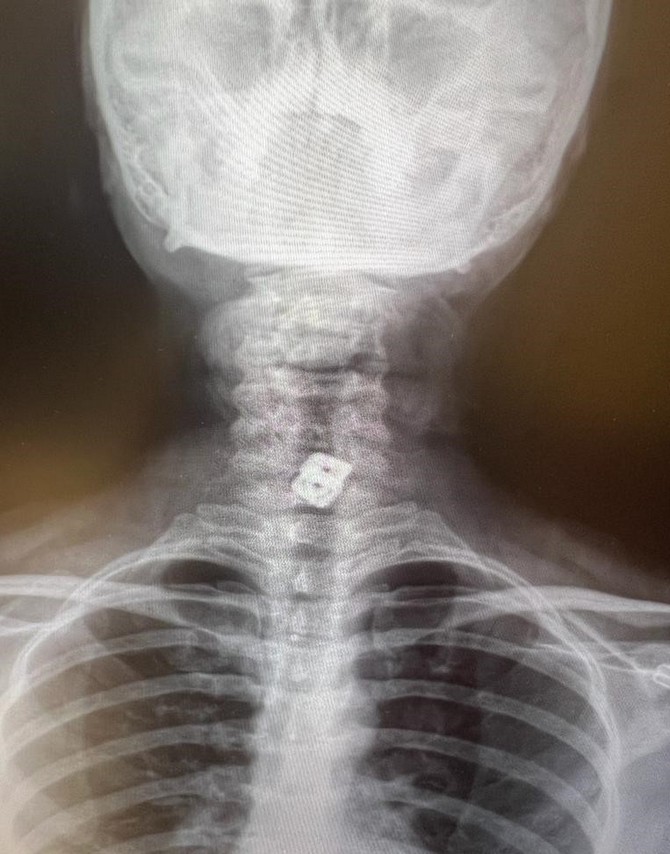

Sultan Tıraş’ın Gaziantep’te başka özel hastanede yapılan radyolojik tetkikler ve değerlendirmeler sonucu daha önce başka bir merkezde boyun omurlarına yerleştirilen metal disklerin yerinden oynadığının saptandığını anımsatan Prof. Dr. Elbeyli, sözlerini şöyle sürdürdü: “O hastanede beyin ve sinir cerrahisi uzmanı tarafından ameliyata alınan Sultan Tıraş’ın boyun omuruna konulan iki aparattan biri çıkarılmış, ancak diğerinin yemek borusunu delip mideye indiği belirlenmiş. İlgili hekim bana ulaşarak bilgilendirmeyi yaptı ve hastayı hastanemize sevk etti.

Yoğun bakıma alınan hastaya yaptığımız detaylı tetkikler ve klinik değerlendirme sonucu mediyastenit (ciddi göğüs enfeksiyonu) saptandı. Bu ciddi bir sorun olup, hayati riski yüksektir. En hızlı şekilde tıbbi tedaviye başladık, gastroenteroloji bölümümüzde endoskopi yapıldı.

Yemek borusunda oluşan delik ve delikten mideye inen metalik cerrahi aparat görüldü. Göğüs kafesi içinde ciddi bir iltihap ve hava birikimi vardı. Hasta yakınları durum ile ilgili bilgilendirildi, riskler kendileri ile paylaşılarak hastamıza tıbbi müdahale edebilmemiz gerekli onayları alındı.”